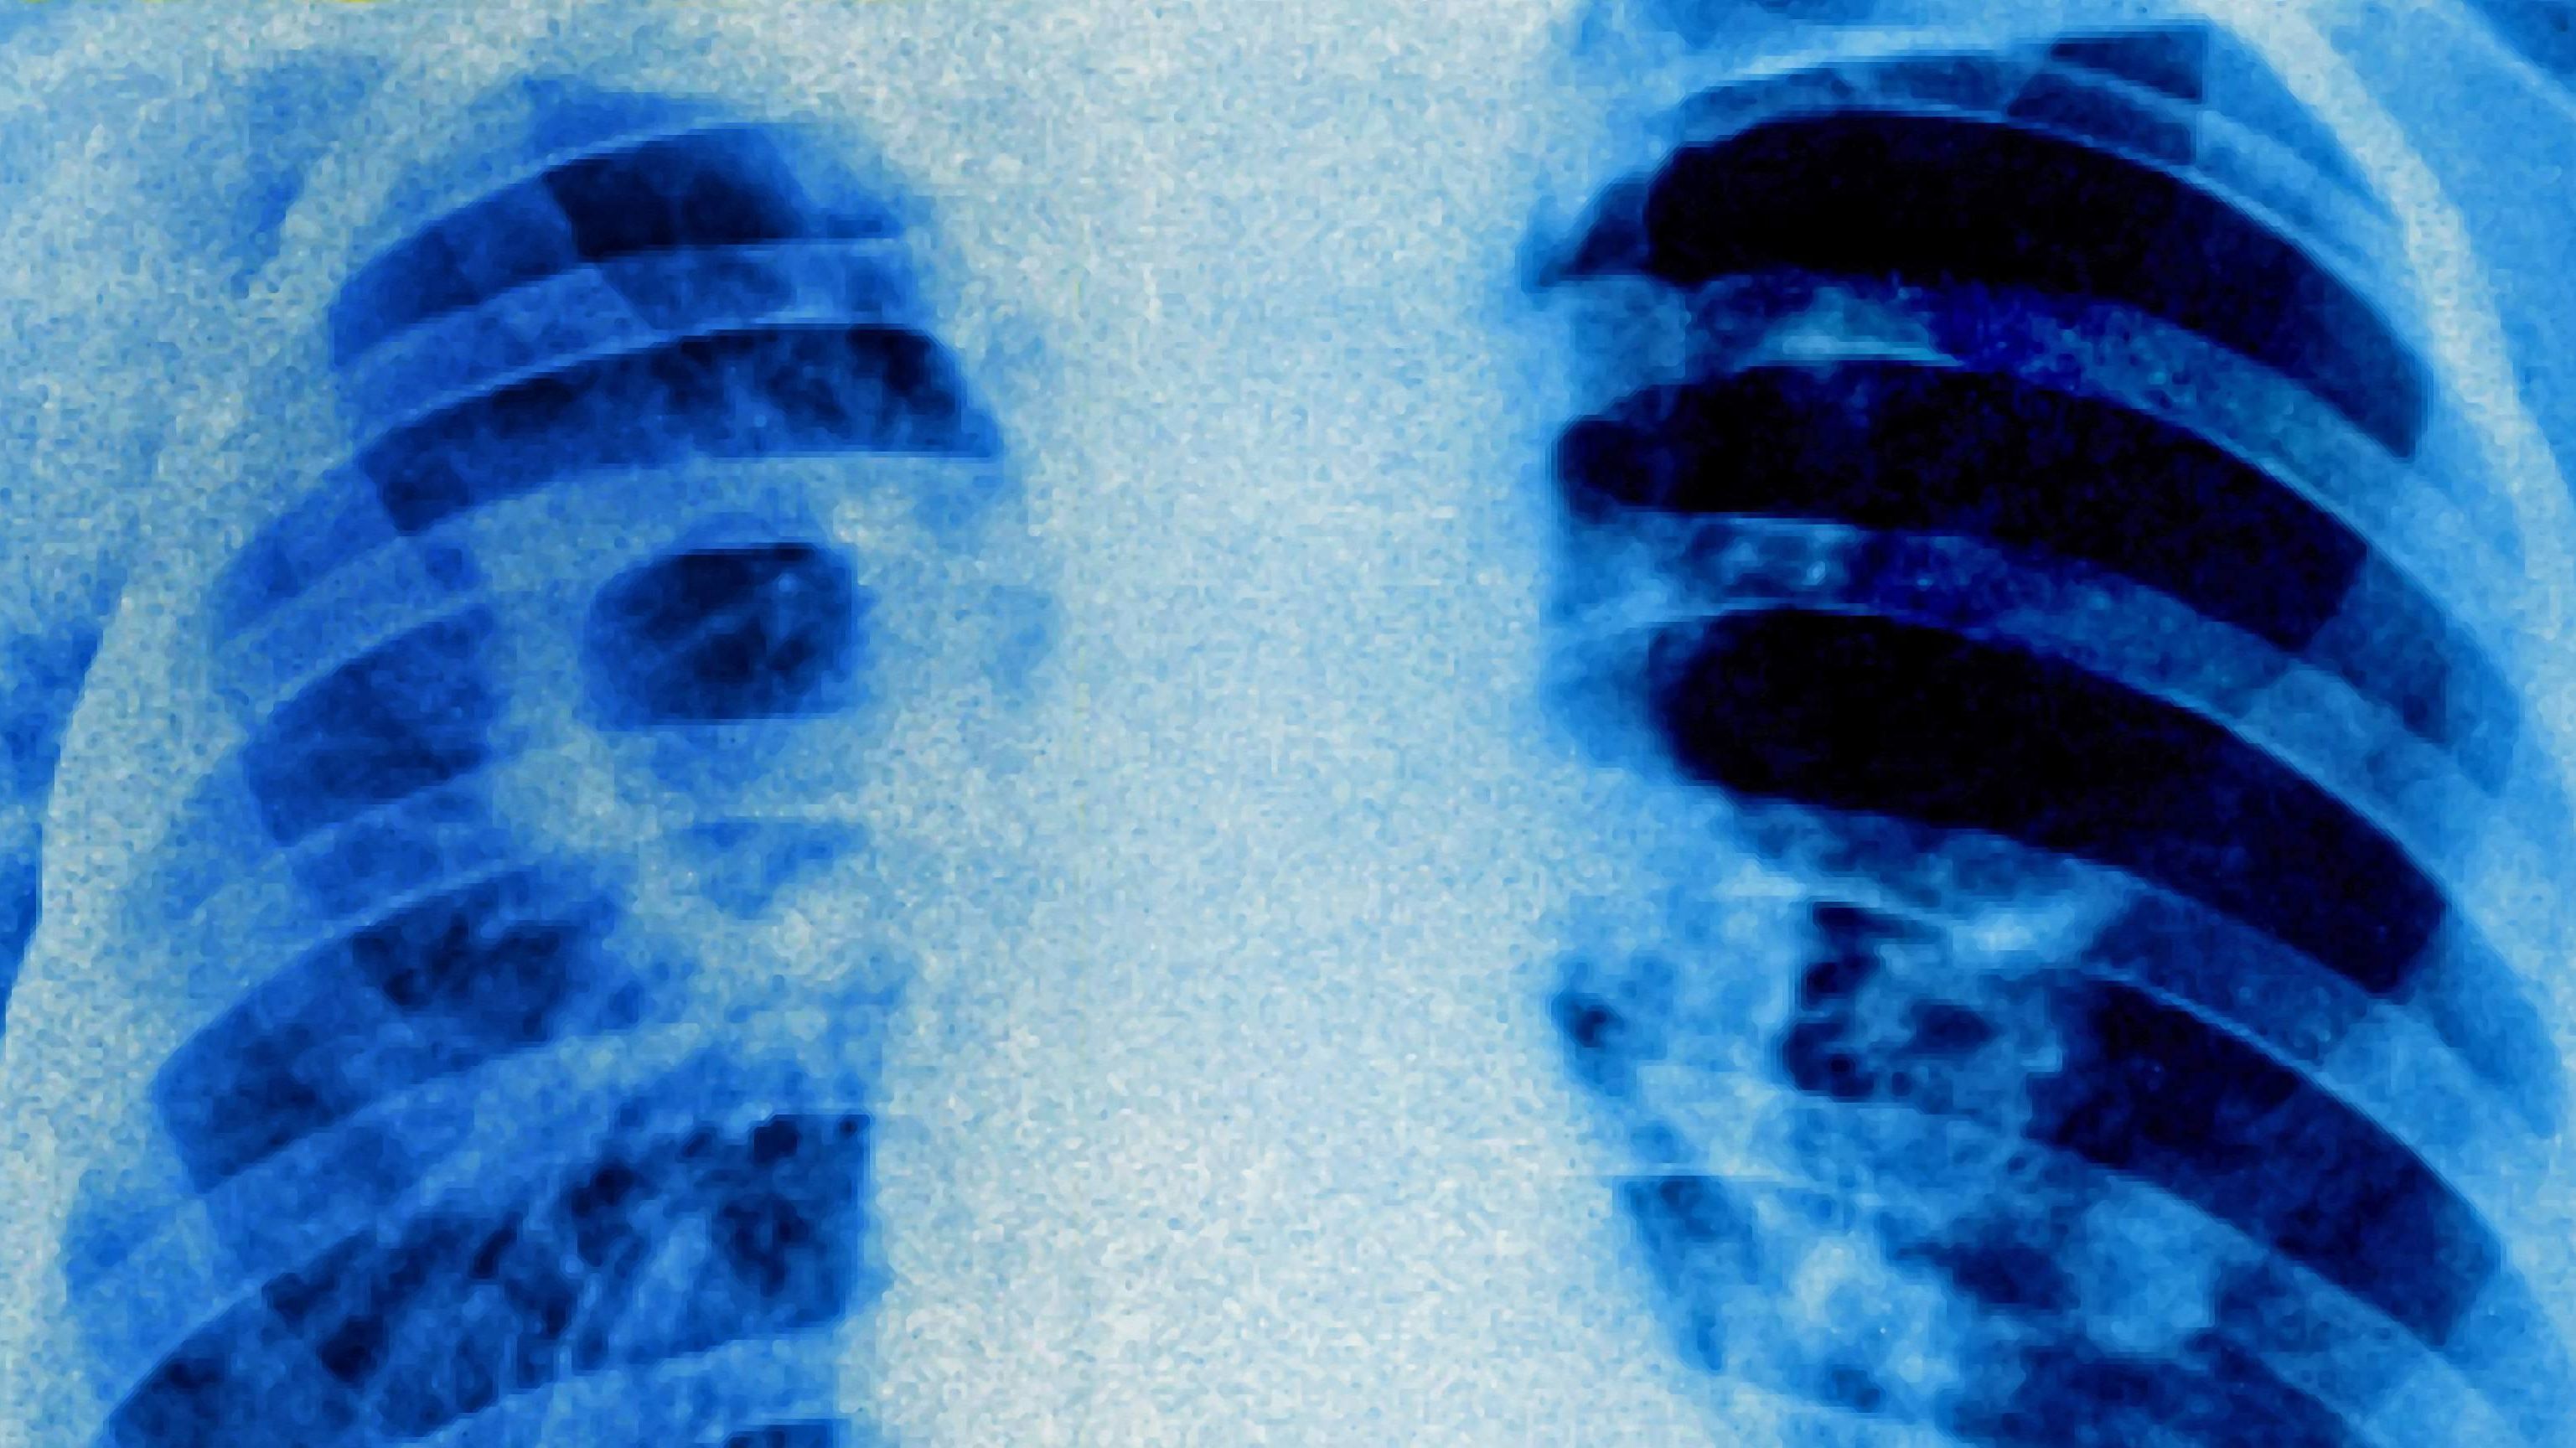

Tbc Inkubationszeit. Jedes jahr bring neue grippeviren hervor. Die inkubationszeitinkubationszeit die inkubationszeit ist definiert als der zeitraum zwischen dem kontakt mit dem krankheitserreger bis zum auftreten der ersten krankheitsanzeichen. Der impfstoff wird jedes jahr neu angepasst. Tuberkulose (tbc) ist eine gefährliche bakterielle infektion. Die tuberkulose (tb) ist eine infektionskrankheit, die durch mycobacterium tuberculosis verursacht wird. Tbc steht immer noch an der spitze der häufigsten tödlichen infektionen auf der welt. Die inkubationszeit , die zeit von der ansteckung bis zum ausbrechen der krankheit, beträgt ca. Die tuberkulose (tbc, schwindsucht) ist eine weltweit verbreitete infektionskrankheit. Like the earlier versions onebag3 will continue to offer powerful options for those who wish to delve a little deeper. Erreger sind mykobakterien, die in erster linie von mensch zu mensch übertragen werden (tröpfcheninfektion). Der zeitraum zwischen aufnahme des bakteriums und dem ausbruch der krankheit tuberkulose kann sehr unterschiedlich sein: Onebag3 addon for world of warcraft tbc (the burning crusade). Neue wissenschaftliche erkenntnis vom grünen chef. Die inkubationszeit (von lateinisch incubatio, „ausbrütung, inkubation, von lateinisch incubare ‚ausbrüten') ist ein begriff aus der infektiologie und beschreibt die zeit, die zwischen infektion mit einem krankheitserreger und dem auftreten der ersten symptome vergeht. Es gibt viele verschiedene arten der grippe.